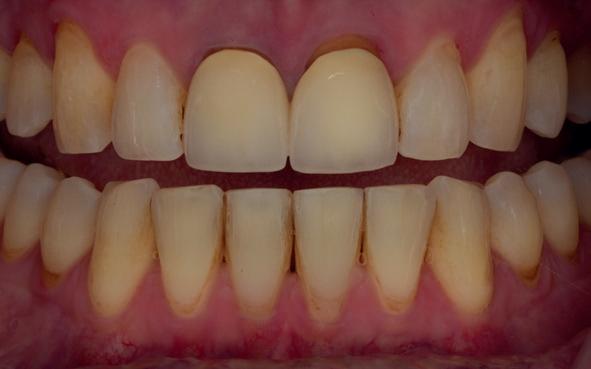

Een 47-jarige vrouw wordt aan het einde van het orthodontische traject door haar eigen tandarts naar mij verwezen voor een intake en eventuele behandeling. Bij mevrouw zijn elementen 12 en 22 afwezig. De 13 en 23 zijn gemesialiseerd. Haar eigen tandarts vraagt of ik het front met composiet kan restaureren om weer een harmonieuze glimlach te krijgen (Afbeelding 1).

Tijdens de intake wordt een complete lichtfoto status gemaakt om de positie van de elementen goed in kaart te brengen en een behandelplan op te kunnen stellen. Op de close-up foto van het bovenfront (afbeelding 2) zien we dat er sprake is van slijtage aan element 11. Elementen 12 en 22 zijn afwezig en elementen 13 en 23 zijn gemesialiseerd. Tussen element 11 en 13 is er sprake van een diasteem. Dit diasteem is niet aanwezig aan de andere zijde (afbeelding 3).

Dit zorgt voor een lastige situatie, omdat bij het sluiten van dit diasteem (dit is de wens van de patiënt) elementen 13 en 11 breder zullen worden dan elementen 21 en 23. Dit is één van de redenen waarom ik patiënten altijd graag aan het einde van het orthodontist traject wil zien. Op dat moment is het nog mogelijk om kleine wijzigingen door te voeren, voordat de beugel definitief wordt verwijderd. Na de intake stuur ik een terugrapportage naar de orthodontist waarbij ik vraag om de elementen zo te positioneren dat de ruimte beter verdeeld is.

Ik zie mevrouw een aantal weken later terug voor evaluatie (afbeelding 4). Er is een klein centraal diasteem ontstaan en daardoor is het diasteem tussen de 11 en 13 ook kleiner geworden. Tussen de 21 en 23 is geen diasteem aanwezig (afbeelding 5), waardoor er hoogstwaarschijnlijk wel iets breedte verschil zal zijn tussen de linker- en rechterzijde.

Met composiet wordt een snelle mock-up gemaakt om te beoordelen of ik in deze situatie goed kan uitkomen met de ruimte, of dat we wellicht de elementen nog meer moeten verplaatsen (afbeelding 6). Mevrouw is zeer tevreden met de snelle mock-up en daarom wordt besloten dat de orthodontische behandeling afgerond kan worden. Eventuele verschillen in breedte kunnen we proberen optisch zoveel mogelijk te maskeren.

Nadat de vaste apparatuur verwijderd is (afbeelding 7 en 8), zie ik mevrouw voor het maken van een afdruk/scan ten behoeve van een wax-up. Aangezien ik in deze casus wil werken met de injectietechniek, is een wax-up noodzakelijk.